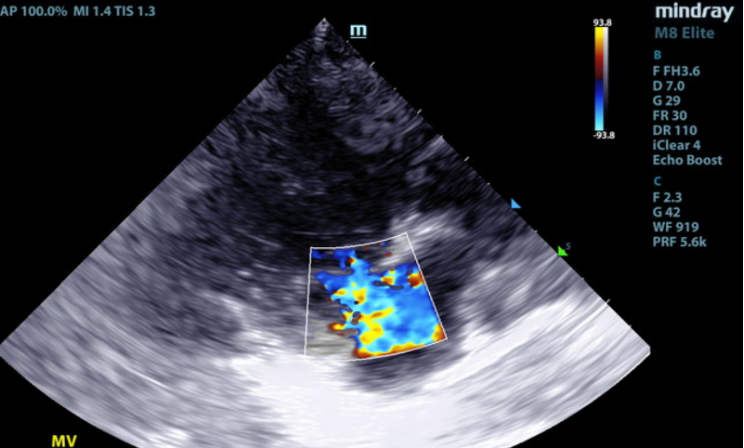

2D, M-mode, color flow, and Doppler imaging is available. The mitral valve is diffusely thickened with prolapse into the left atrial lumen. There is moderate eccentric mitral regurgitation present.

There is moderate left atrial enlargement. There is mild left ventricular dilation. Left ventricular systolic function is adequate. There is normal systolic flow velocity across the aortic valve; no insufficiency. The aortic valve appears normal. Mild right atrial/ventricular enlargement. The tricuspid valve is mildly thickened with moderate tricuspid regurgitation. The tricuspid regurgitant velocity is consistent with moderate to severe pulmonary hypertension (PH). The pulmonary artery is prominent. Normal aortic and pulmonic outflow velocities. No aortic insufficiency (AI) or pulmonary insufficiency (PI). No pericardial/pleural effusion or cardiac masses are seen.